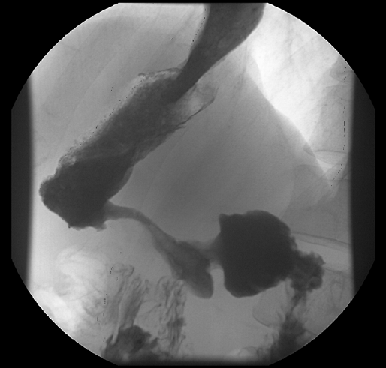

Во-вторых, своеобразие рентгено-эндоскопических данных — диффузное изменение стенки желудка с развитием ригидности, циркулярного сужения (желудок изменен по типу кожаного сосуда) (рис. 1), утолщения стенок и плохого расправления складок на фоне инсуфляции воздуха. Своеобразие морфологической картины — гнездное включение опухолевых клеток в виде очагов в слизистую оболочку желудка с диффузной инфильтрацией слоев на фоне выраженной стромальной реакции с развитием интерстициального фиброза. Отличны подходы к тактике хирургического и комбинированного лечения. Однако главным отличием данной формы рака желудка является крайне неблагоприятный прогноз. Абсолютное большинство пациентов поступают на лечение в распространенных стадиях заболевания. Истинно радикальные вмешательства удается выполнить крайне редко, что отражается на отдаленных результатах — 5 лет наблюдения переживает не более 5% пациентов. Основным видом прогрессирования после радикального лечения является интраперитонеальный рецидив в виде канцероматоза брюшины.

Рисунок 1. Тотальный рак желудка